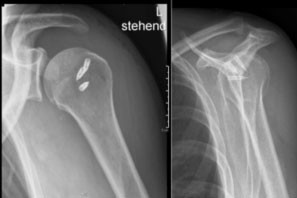

Postoperatives Röntgenbild der Schulter nach Refixation der Rotatorenmanschette mit Nahtankern

Ist die vorliegende Verletzung der Rotatorenmanschette operabel, dies ist abhängig vom Grad der Retraktion der Sehne sowie der Muskelqualität (wenig fettig degeneriert), werden die entsprechenden Sehnen mit Hilfe von sogenannten Knochenankern am zuvor angefrischten Knochen des Oberarmkopfes fixiert. Im Anschluss ist je nach Verletzungsmuster ein spezielles Nachbehandlungsschema unter physiotherapeutischer Anleitung durchzuführen.